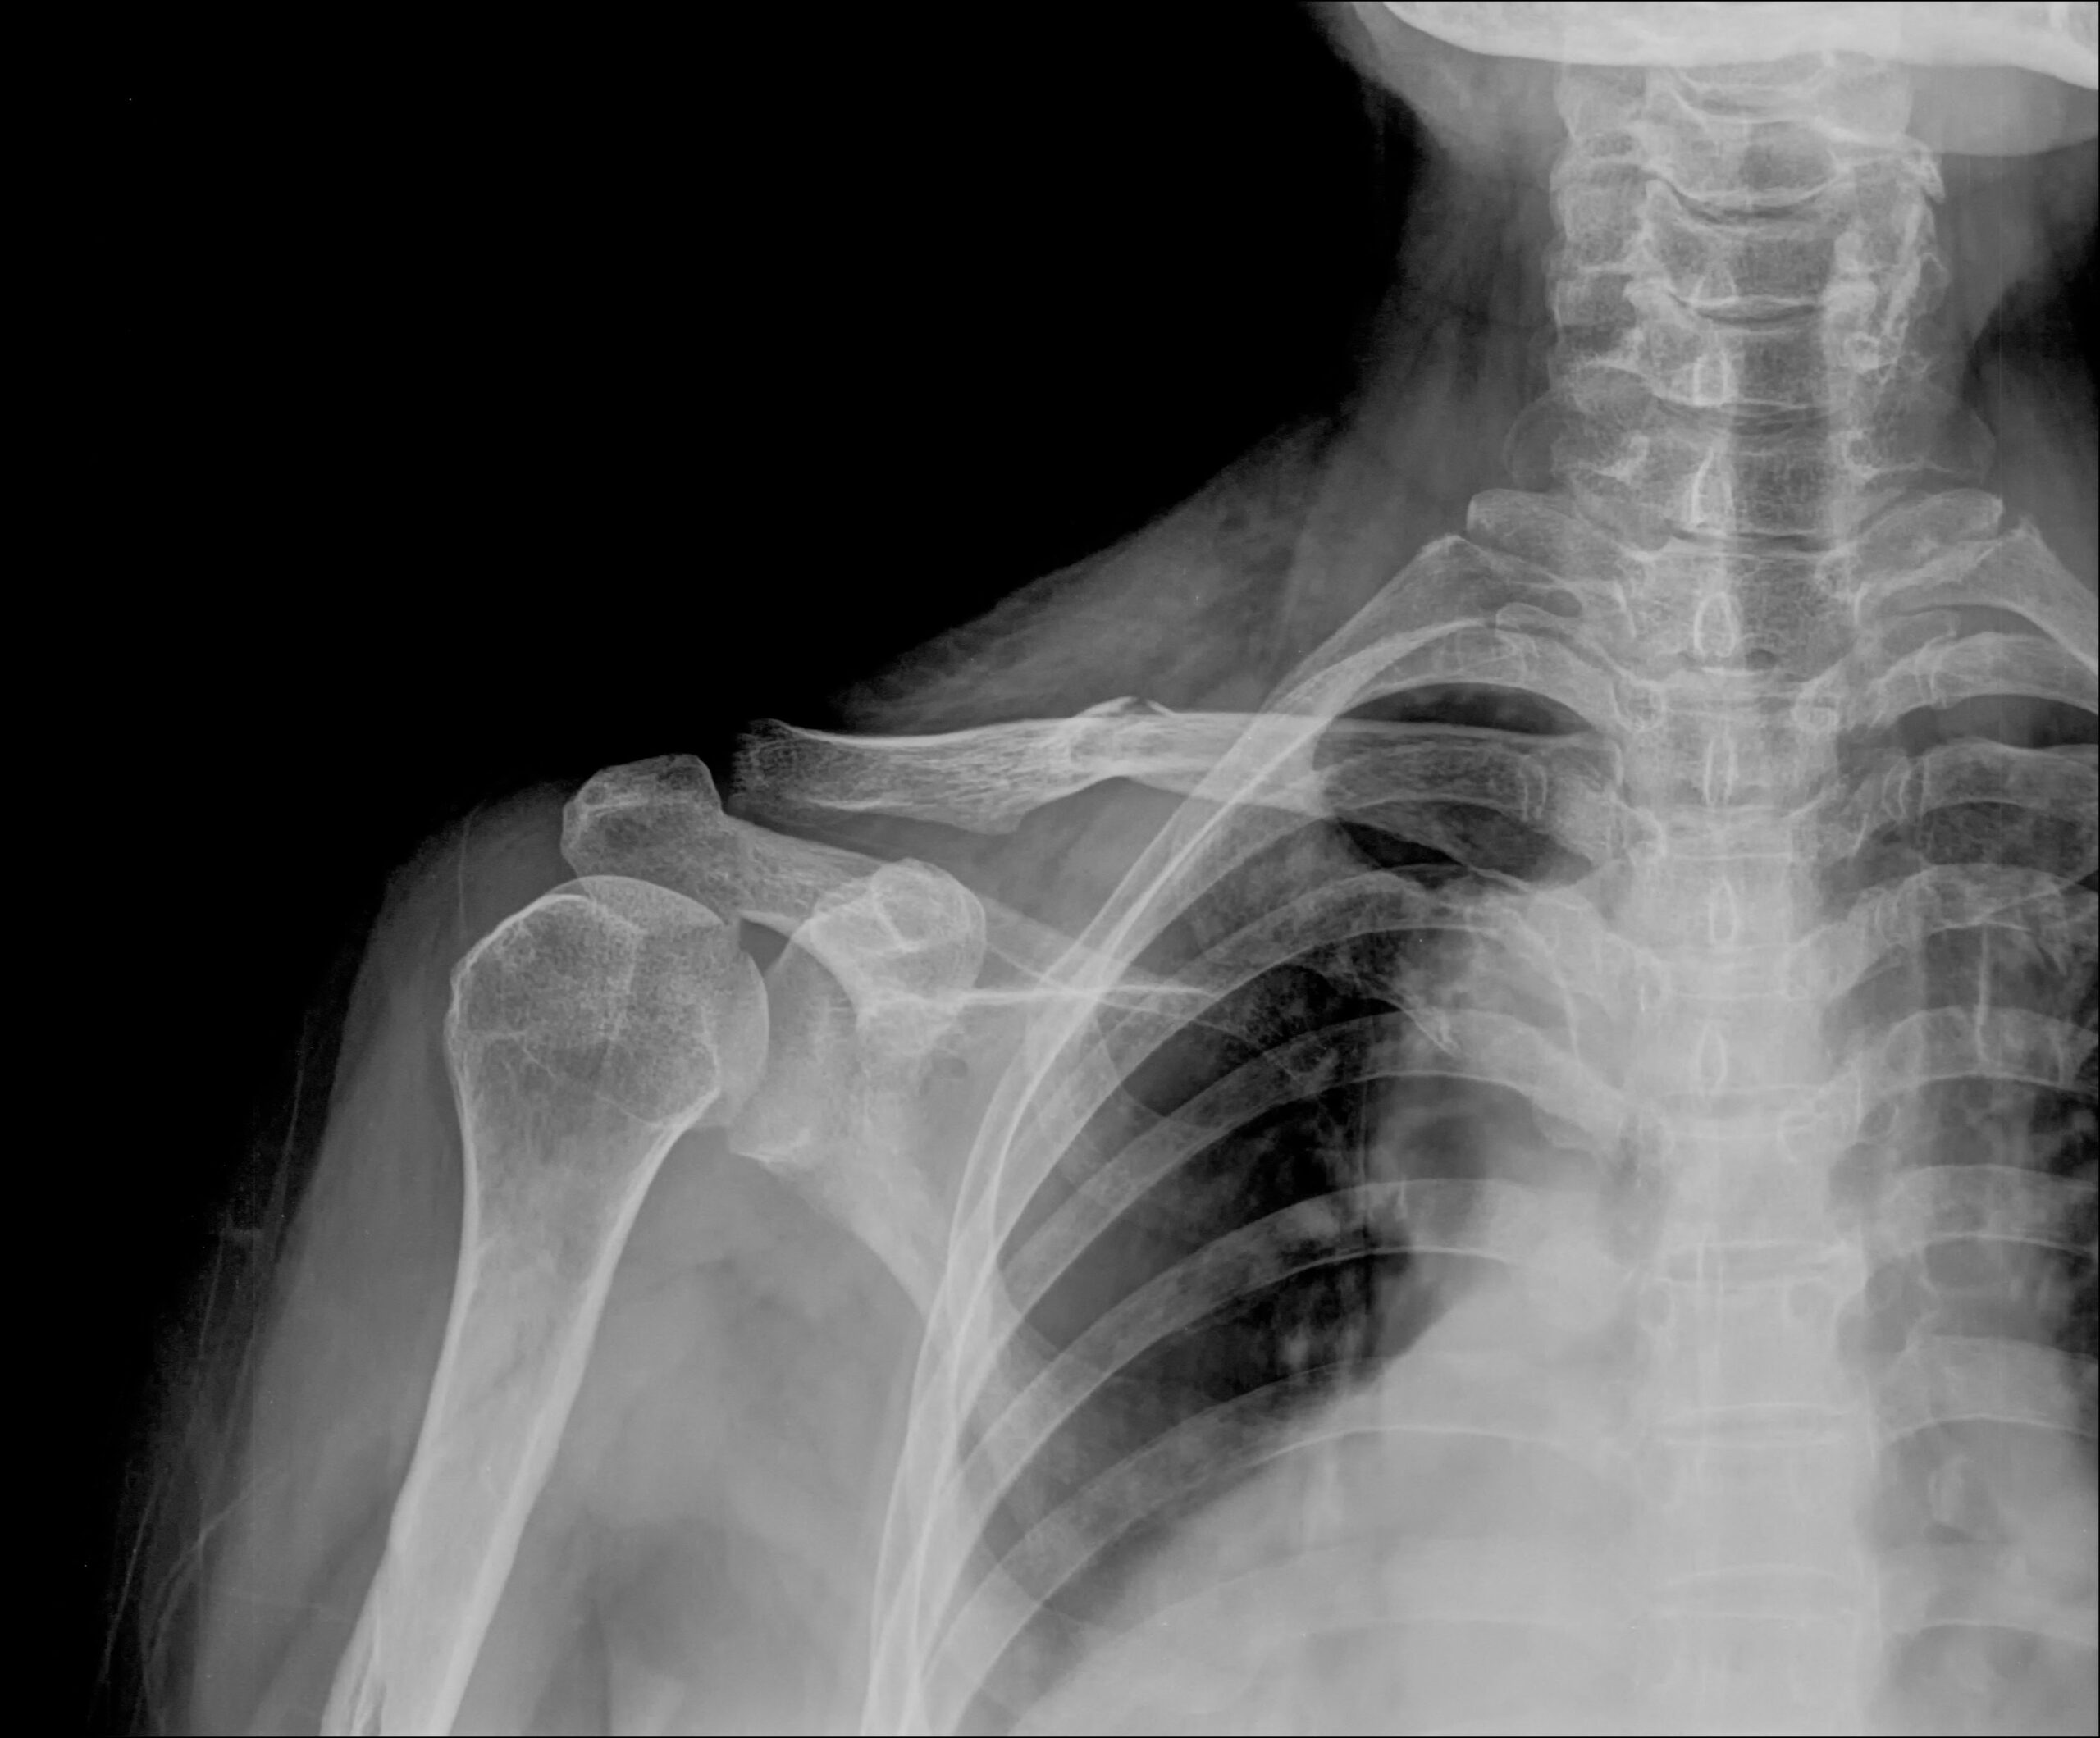

The AP (Anteroposterior) View of the Clavicle is a standard X-ray projection used to evaluate the entire length of the clavicle (collarbone), including its sternal and acromial ends. In this view, the patient is positioned either standing or lying supine, with the X-ray beam directed from front to back (anterior to posterior) and centered over the midshaft of the clavicle. This projection provides a clear image of the clavicle’s alignment, cortical continuity, and any possible fractures, dislocations, or bone lesions. It is commonly used in trauma cases and is often complemented by a cephalic tilt (AP axial) view for better visualization of overlapping structures.

AP view